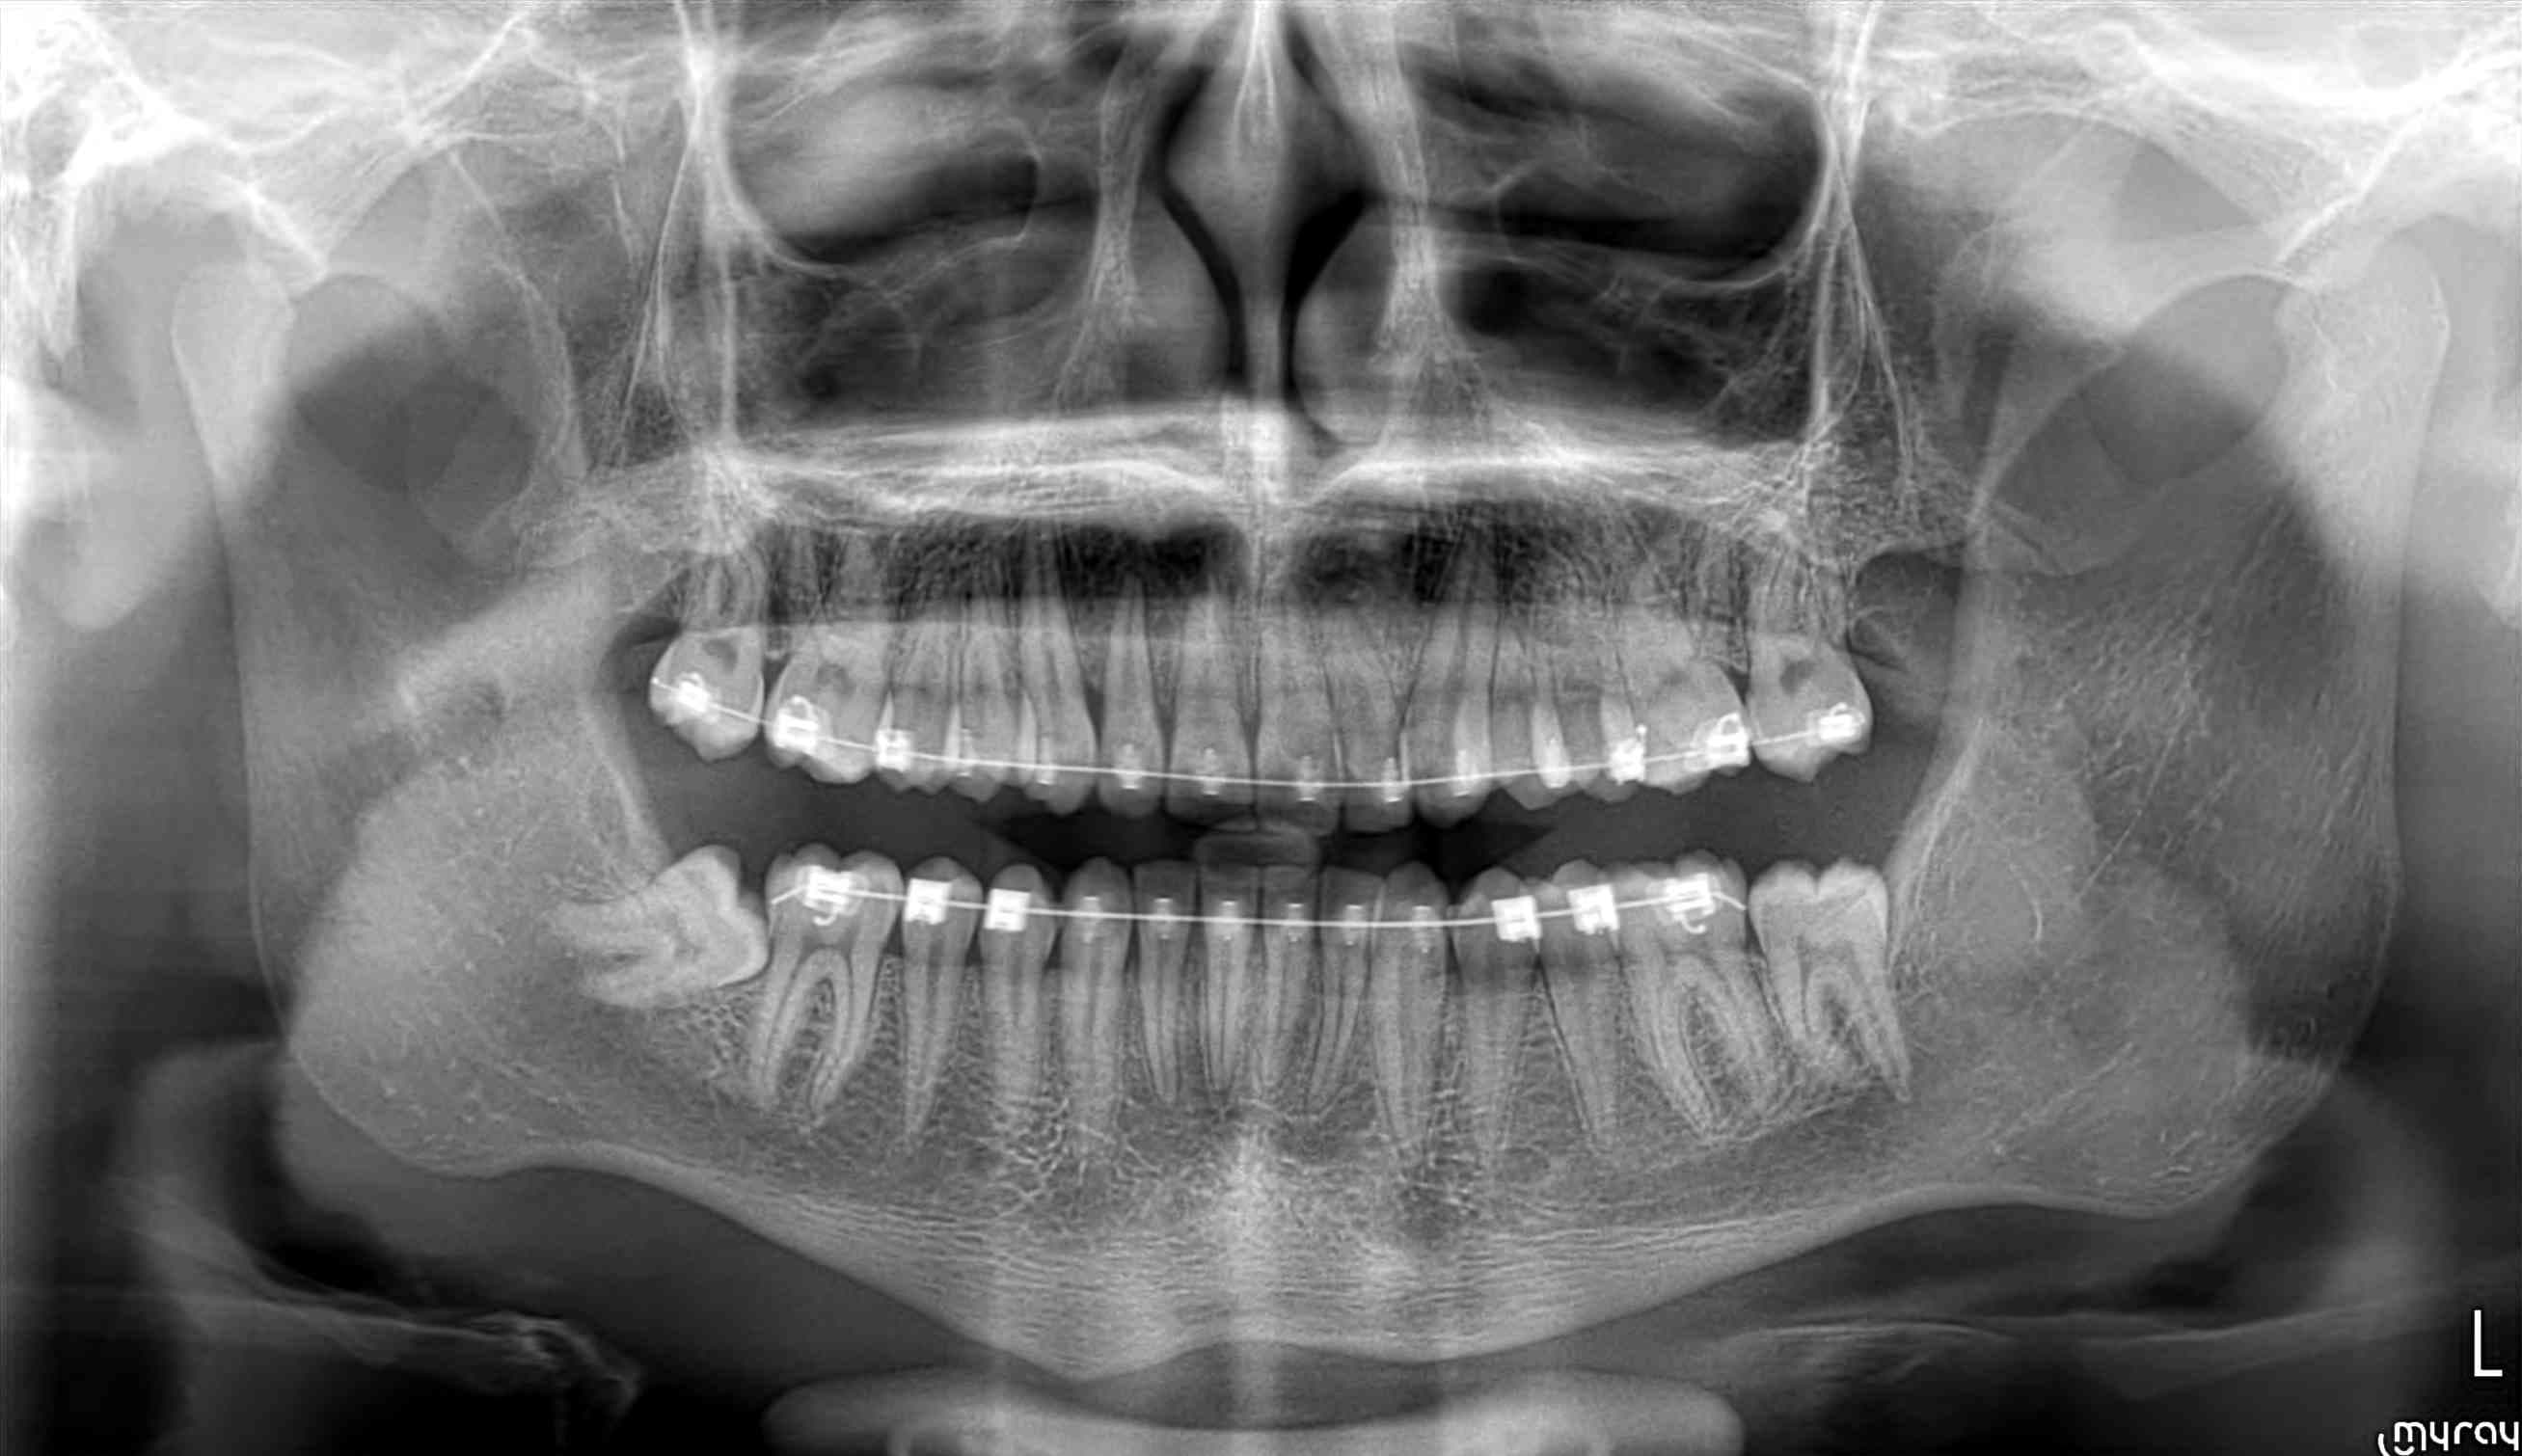

Une ortho me demande de procéder à l'extraction de la 47 sur un enfant de presque 18 ans.

Qu'en pensent les spécialistes ortho du forum ?

1 - oui il n'est pas possible de redresser ce genre de dent ?

2 - de toutes façons, y'a pas la place pour que cette dent soit correctement en place en particulier au niveau gingival.

A côté de ça, redresser la dent ok, et ensuite ? Quelle place disponible ? Regardez la 37, elle est bien dans l'axe, et pourtant son arrivée sur l'arcade semble incertaine aussi par manque de place ! Redresser c'est bien beau mais s'il n'y a pas la place de toutes façons...

Bref, le plus simple reste d'en parler directement avec l'ortho. Il a vu le patient en bouche, il a d'autres documents que juste une pano (et encore bravo à ceux ici qui arrivent à faire un plan de traitement avec juste ça, moi j'en suis bien incapable), il pourra t'expliquer les raisons de son choix.

Concrètement franchement là comme ça je ne sais pas. J'ai envie de dire qu'il aurait fallu envisager d'extraire 35 et 45 peut-être, pour pouvoir être sûr de mettre les 7 sur l'arcade, mais ça c'était une question qu'il aurait mieux valu se poser au démarrage, pas à ce stade-là du traitement. Ca aurait permis d'avoir au moins une partie des 7 mandibulaires en contact occlusal avec les 7 maxillaires (alors que là si on se retrouve à extraire une 7 il faudra aussi probablement faire sauter l'antagoniste, ce qui est bien ennuyeux).

Je ne vois pas comment on pourrait mettre tout ce petit monde en place sur l'arcade proprement. Là au mieux tu vas finir avec la face distale de 37 et 47 sous un capuchon muqueux, à moitié bloqué par la branche montante de la mandibule, ça va juste générer des abcès comme une dent de sagesse mal sortie et au bout du compte une belle carie sur une dent qui sera bien difficilement restaurable par le dentiste puisqu'à moitié dans la gencive.

37 a déjà limite la place , propice pour avoir des péricoronarites.

47 si bien remise en place : même sanction. Et encore sacrée galère pour la mettre comme il faut en occlusion avec 17. À extraire

Le redressement est techniquement possible, mais je rejoins l'équipe extraction à cause du manque de place, avec exactement les mêmes arguments que Doagui (et effectivement il aurait peut être fallu se poser la question de l'avulsion de prémolaires au départ, mais maintenant c'est trop tard).

Il n'est pas tant question de technique ou de faisabilité que d'intérêt final. Ce cas n'a rien à voir avec celui que tu présentes en panoramique, l'espace disponible n'est pas du tout le même.

Une radio panoramique ne me paraît pas suffisante dans ce cas-ci pour décider de supprimer 4 molaires dont 3 sont déjà sur l'arcade.

Il y aura exactement le même espace que pour sa 37 . Avec en D un beau fourre-tout propice aux pericoronarites. Même pas besoin de voir en clinique ce qu’il se passe . On voit bien la portion osseuse en D de 37 qui longe la dent. Avec une sonde paro on doit y enfoncer l’équivalent d’1 cm.

Totalement d’accord avec Doagui , faut comparer ce qui est comparable. Quant à l’histoire de la branche montante qui est en V par rapport à l’arcade ....... il y a juste à regarder la lamina dura qui se prolonge en D de la 7 pour comprendre qu’on a 1 cm de fausse poche favorable à la mise en place de plaque dentaire propice à une inflammation carabinée gingivale que le patient ne pourra JAMAIS nettoyer sans l’intervention d’un insert à détartrer. Dans ton cas Dancha le patient peut nettoyer la zone . Dans l’autre cas il est tout bonnement impossible de nettoyer la zone.